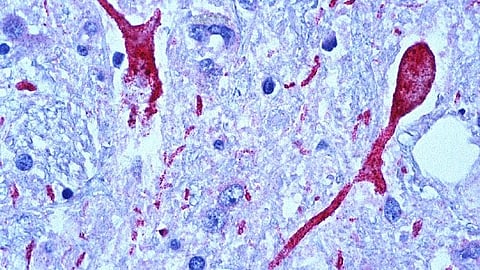

AURORA scientists have known that only a subset of trauma survivors develop PTSD, and that PTSD is associated with increased sensitivity to threats and decreased ability to engage neural structures retrieving emotional memories. Yet how these two processes interact to increase risk for developing PTSD is not clear. To better understand these processes, Murty and colleagues characterized brain and behavioral responses from individuals two weeks following trauma.

Using brain-imaging techniques coupled with laboratory and survey-based tests for trauma, researchers found that the individuals with less activity in their hippocampus and greatest defensive responses to startling events following trauma had the most severe symptoms.